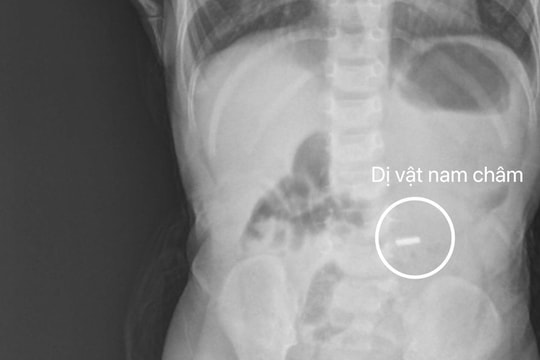

Gắp dị vật nam châm ở tá tràng cho bé trai 18 tháng tuổi

PLBĐ - Sau khi được các bác sĩ thăm khám và chụp X-quang, xác định có hình ảnh dị vật cản quang nằm trong tá tràng, bệnh nhi được chuyển đến Trung tâm Nội soi để tiến hành nội soi cấp cứu, gắp dị vật là nam châm kích thước 6x6mm tại tá tràng D2 ra ngoài.